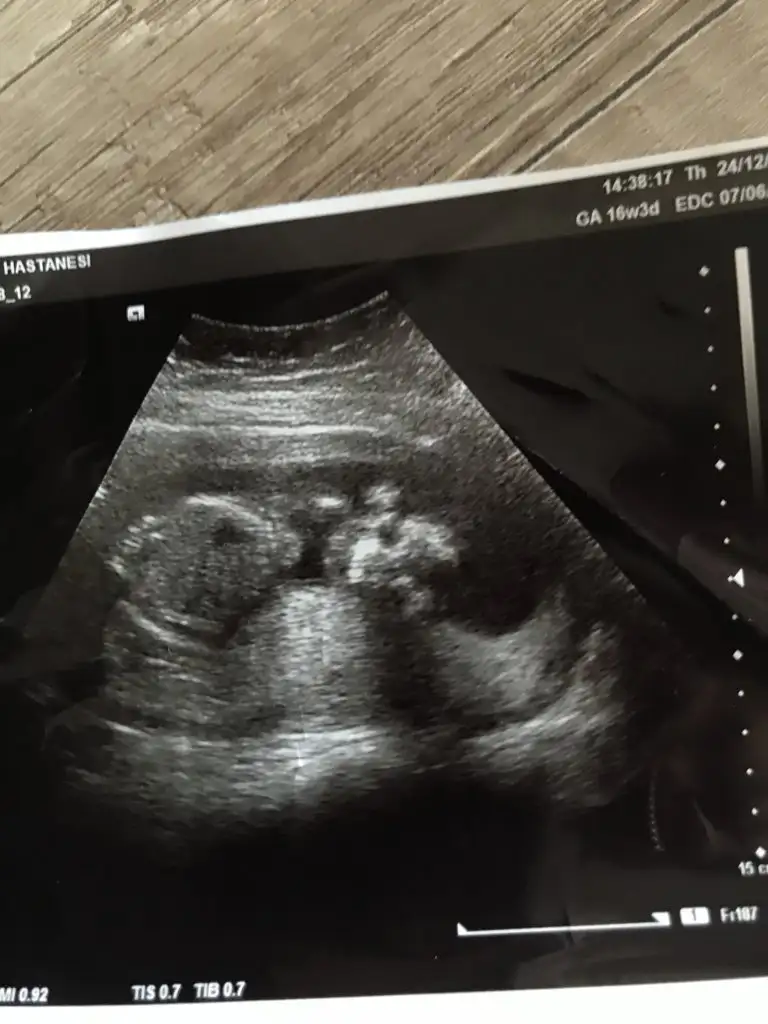

Cinsiyet

Hmmö şimdi anladım cnm peki ne dıyosun kızçe mi 🙄🥰

Kalça tarafı daha yuvarlak gibi geldi o yüzden kız dedim ama tabii daha çok küçük

Canm birde buna bakar mısın teyzesi 17 haftalık olduk doktor erkek gibi çıkıntısı var ama göbek kordonu izasında dedıedaya bakar mısın

Ben goremedım cnm nerde çıkıntı var cinsiyet organı belli mi bu üst fotoda

Hayır canım organdan değil çıkıntılar erkeklerde daha dik kız bebeklerde daha oval oluyor. Bende sağlıkçı değilim gördüğüm ultrasonlardan yola çıkarak tahmin sadece